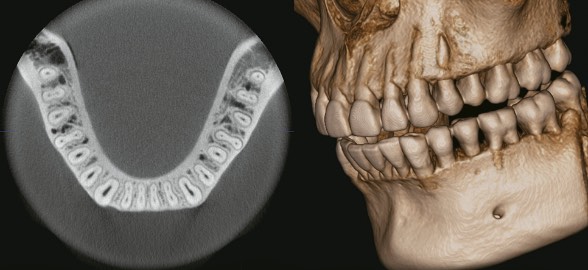

¿Te parecen sorprendentes los progresos de la radiología? ¡A nosotros sí!

¡La impresión 3D dental está revolucionando el mundo de la odontología gracias a su precisión y calidad en los resultados!

Actualmente muchas clínicas dentales y odontólogos se encuentran en proceso de transformación digital y tienen algunas dudas u objeciones respecto a que tan útil es adquirir un